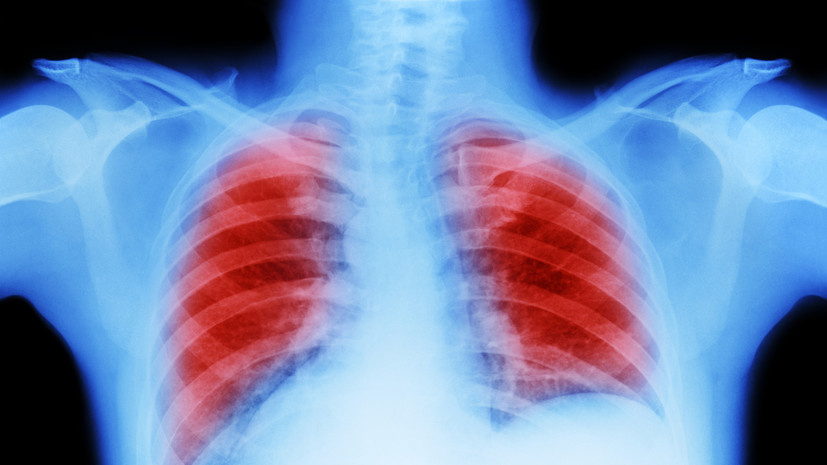

Врач Авдеев рассказал о перспективных методах лечения обструктивной болезни лёгких

Gettyimages.ru